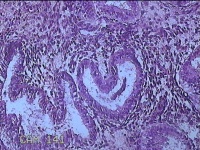

子宫腔赘生物

性别

女

年龄

33岁

临床诊断

子宫内膜息肉?子宫异常出血

一般病史

阴道流血12天。

标本名称

大体所见

灰白粉红色不规则肿物1.5x1.3x0.2cm一堆,表面糜烂。

图2